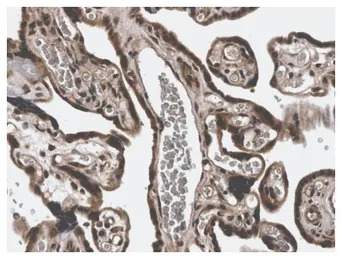

IHC-P analysis of formalin fixed human placenta tissue using GTX52474 MMP3 antibody [3E44].